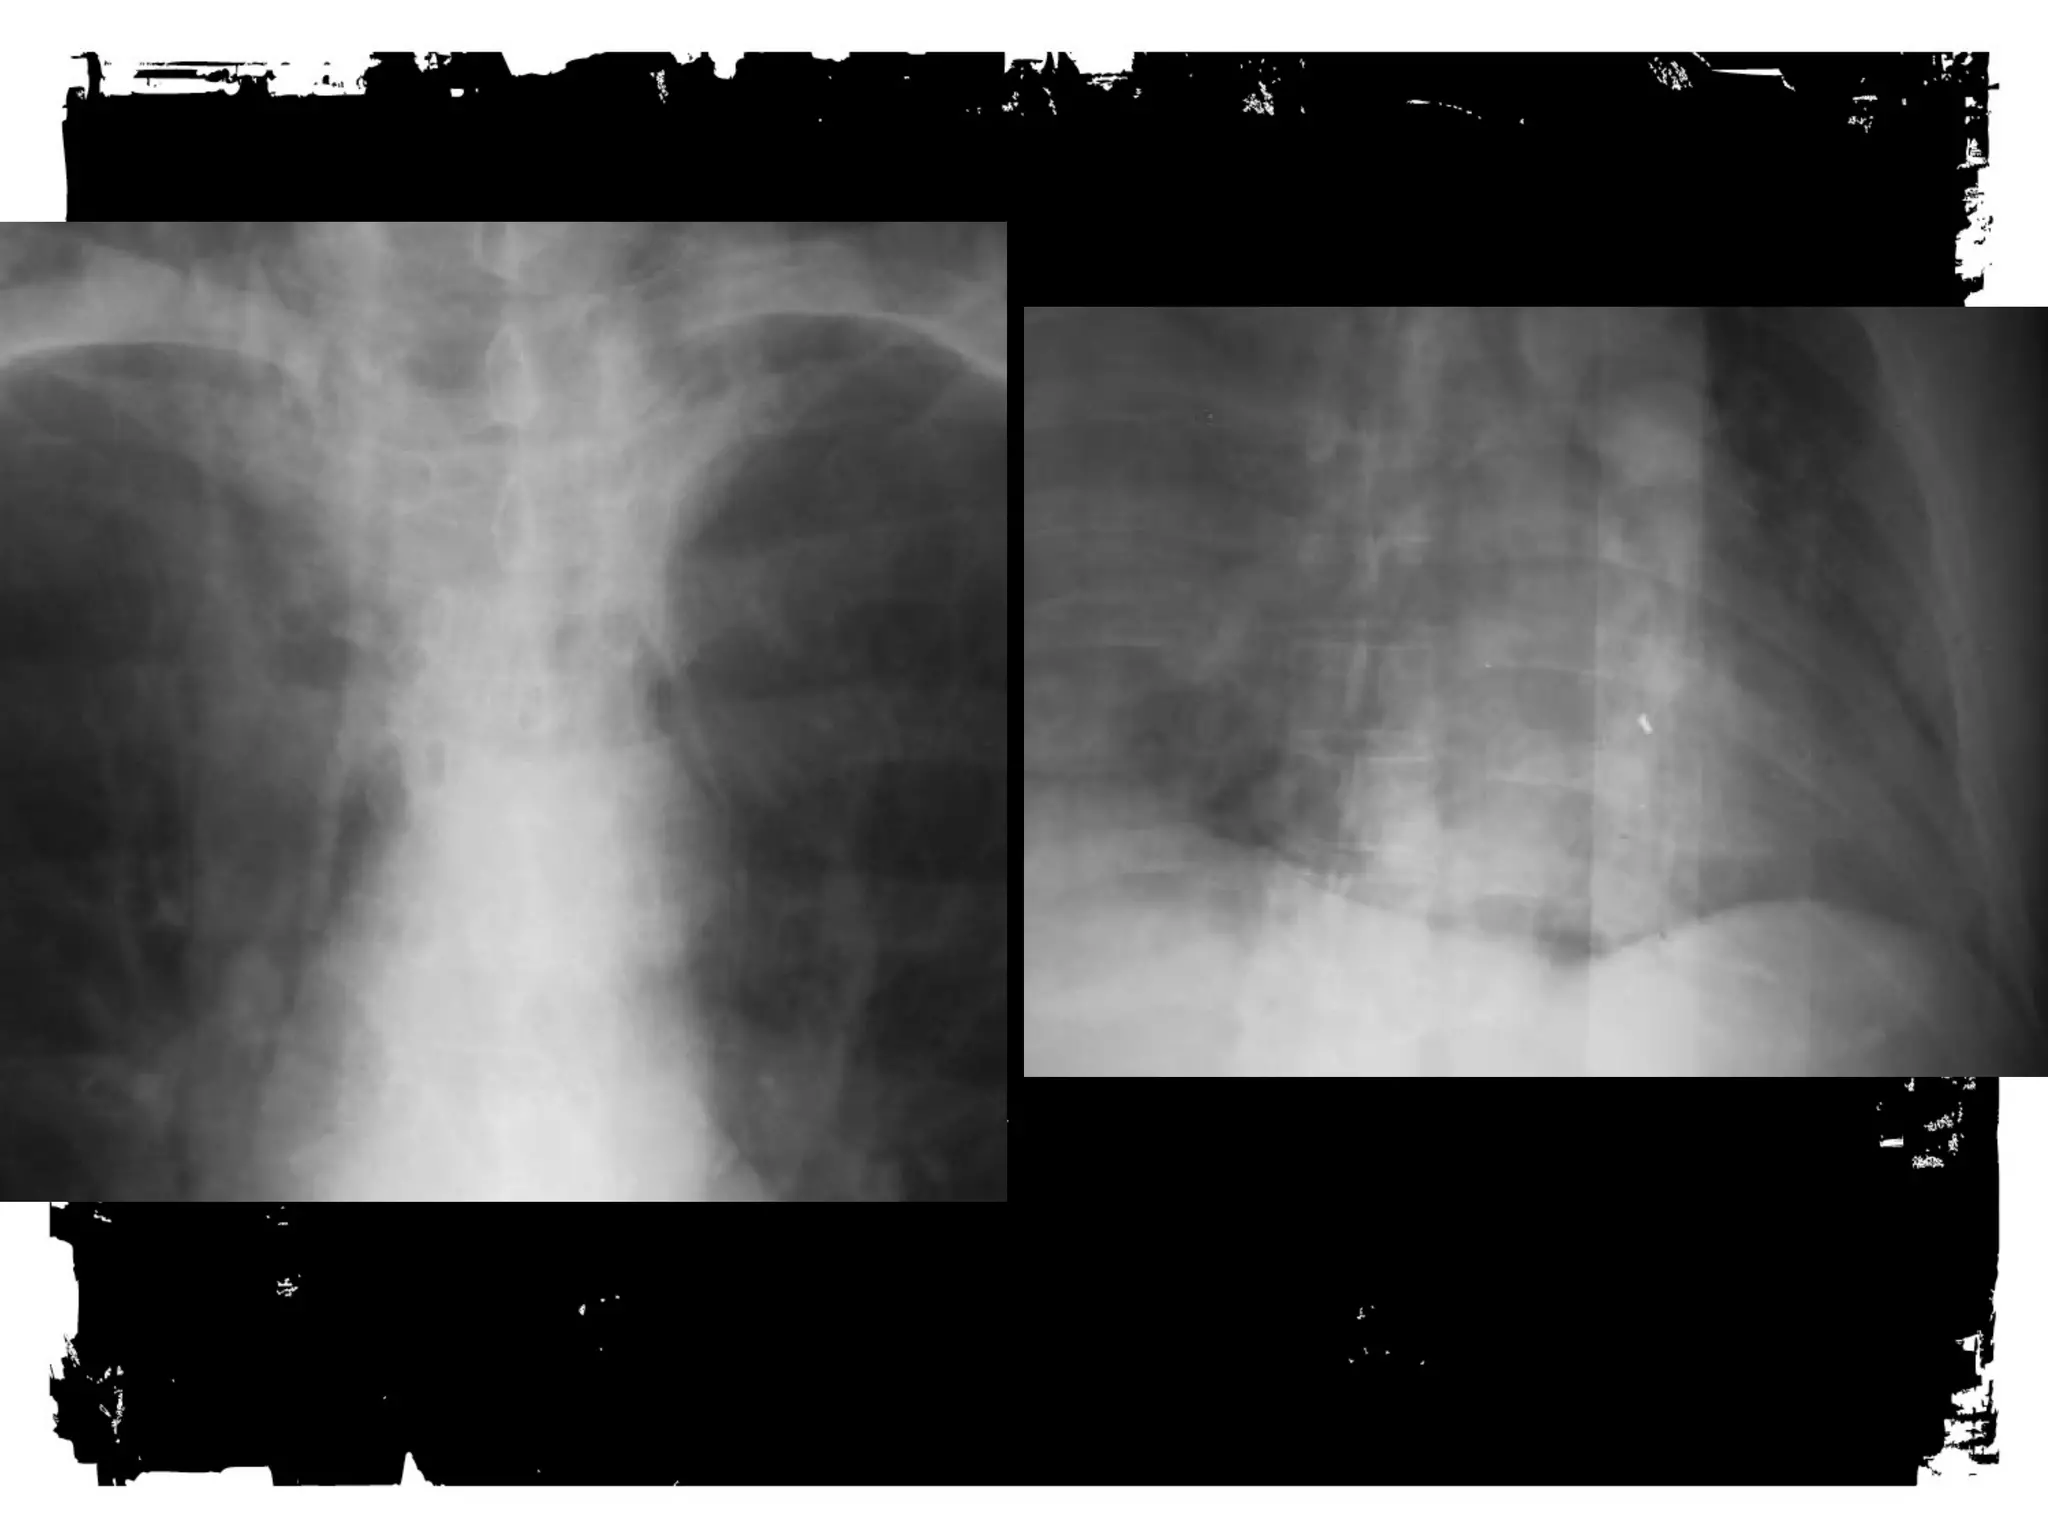

Thoracic Spine Injuries

Rigid

Spinal canal narrower than cervical or lumbar spine

Large spinal cord diameter relative to canal

diameter increases the risk of cord injury

Injury, usually significant (complete), less common

than in other regions

Association between fractures of the thoracic spine

and severe pulmonary injuries, mediastinal

hemorrhage

Compression fracture

Injury to anterior column due to anterior or lateral

flexion

Middle and posterior columns remain intact

X-ray - decreased height anterior vertebral body, post

body height normal

Amount of anterior compression usually less than

40% of post body height

Clinically - stable, cord injury rare

Burst

• Disruption of the middle column

• Mechanism- axial loading

• Varying degrees of retropulsion

into the

neural canal

• X-ray- spreading of post elements

• If post elements involved- 50%

have neuro

injury

• Neurologic injury more common in:

– Loss of vertebral ht > 50%

– Angulation > 20 deg

– Canal compromise more than 40%